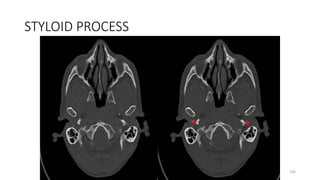

STYLOID PROCESS

87

96

106

Styloid process, base

121